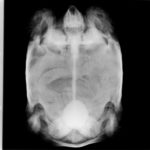

当院はウサギ・小動物・爬虫類・鳥類などのエキゾチックアニマル専門の病院です。

エキゾチックアニマルの診療

専門的なエキゾチックアニマル診療を提供しています。爬虫類、鳥類、小動物など、幅広い種類に対応。専門知識と経験を活かしたケアを提供。

ヒョウモントカゲモドキ、クサガメなどはこちら